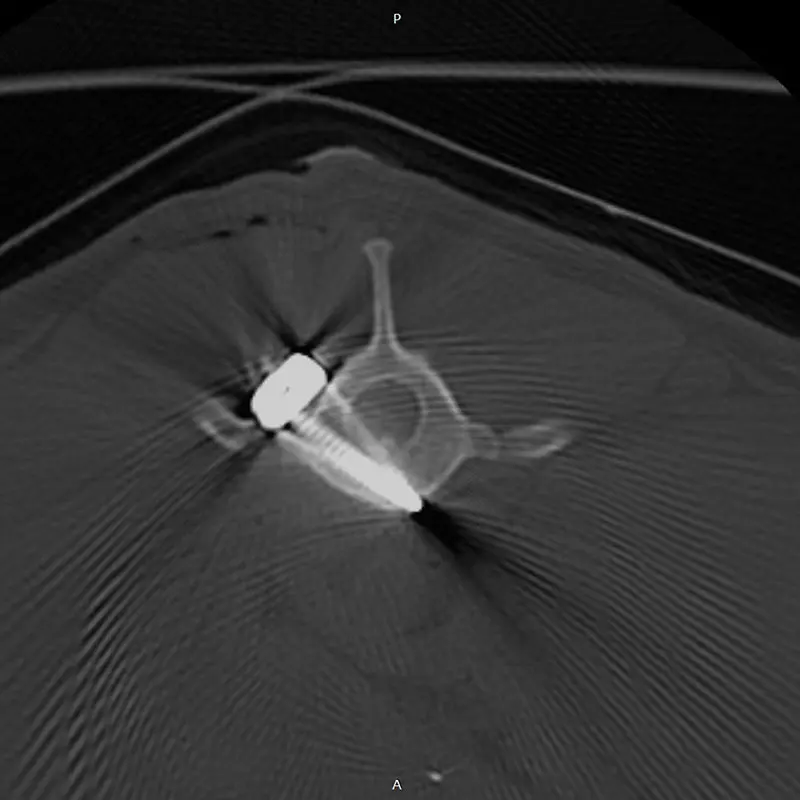

We have been using the system for years, and clinical experience greatly supports its reliability, even in difficult, challenging situations. It is excellent for stabilizing the spine, especially in the thoraco-lumbar region. If the connecting rod is placed ventrally from the articular processes, the screws are placed in the vertebral body at a 45-degree angle at the base of the transverse processes, so that they grip the largest possible bone material. (see CT images). Up to 2 clamps can be attached to a vertebral body from one side. Compared to other, more complex, multi-piece spinal stabilization systems, it is thinner and fits better on the surface of the bone. The screw axis is located ont he side of the axis of the connecting rod (the rod and the screw are not located on top of each other), the clamps can be rotated and slid, so that the largest possible bone stock can be freely accessed during surgery.

In our case, we stabilized the T13-L1 vertebral luxation of a 4-year-old dachshund, where the ligament system of the vertebral body was damaged during a car accident.